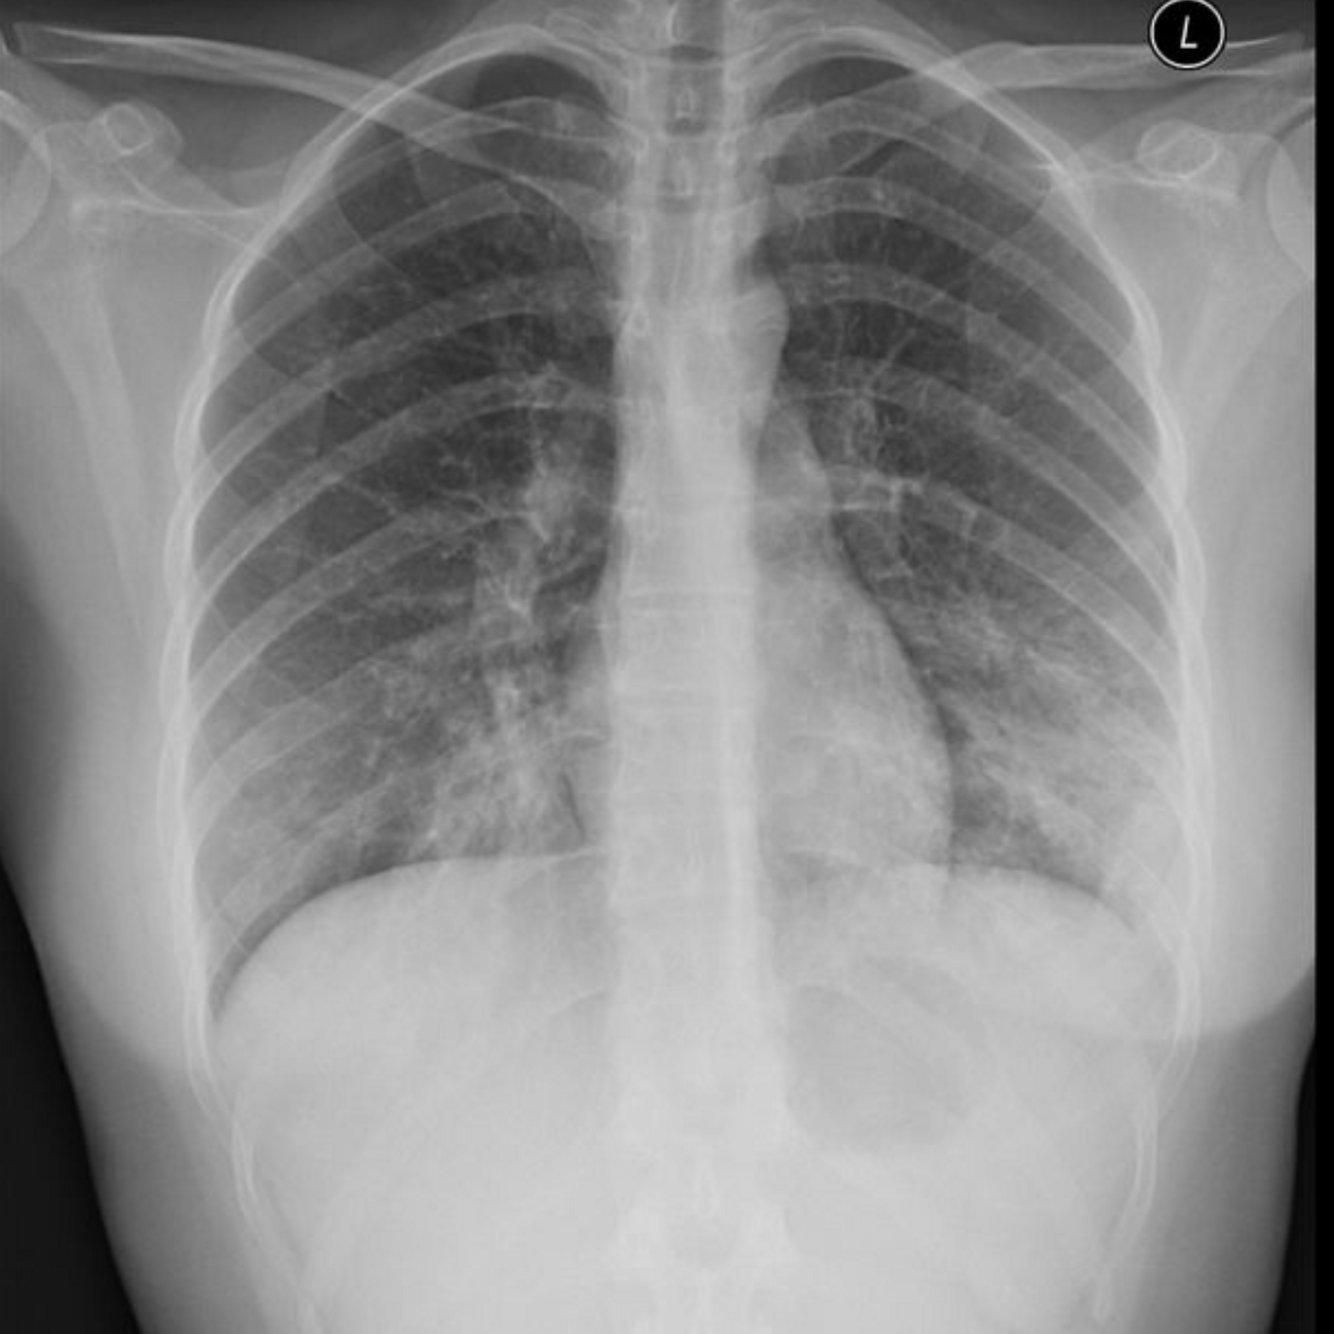

20 F, originally from the Philippines, presents with 4 weeks of cough, fever, night sweats, and 5 kg weight loss.

He reports mild hemoptysis.

T 38.3°C, HR 95, RR 20, BP 110/70, SpO₂ 95% RA.

Exam: mild crackles over the right upper lung.

CXR >

Most likely diagnosis?

How is diagnosis confimed?

A

Pulmonary TB ~Mycobacterium tuberculosis.

Gold standard for diagnosis:

- Sputum AFB smear & culture 3 x early-morning samples

Others:

1. NAAT / PCR

- Rapid detection + rifampin resistance

1. TB skin test (TST) or IGRA Detects latent infection

2. HIV testing

- Co-infection risk high